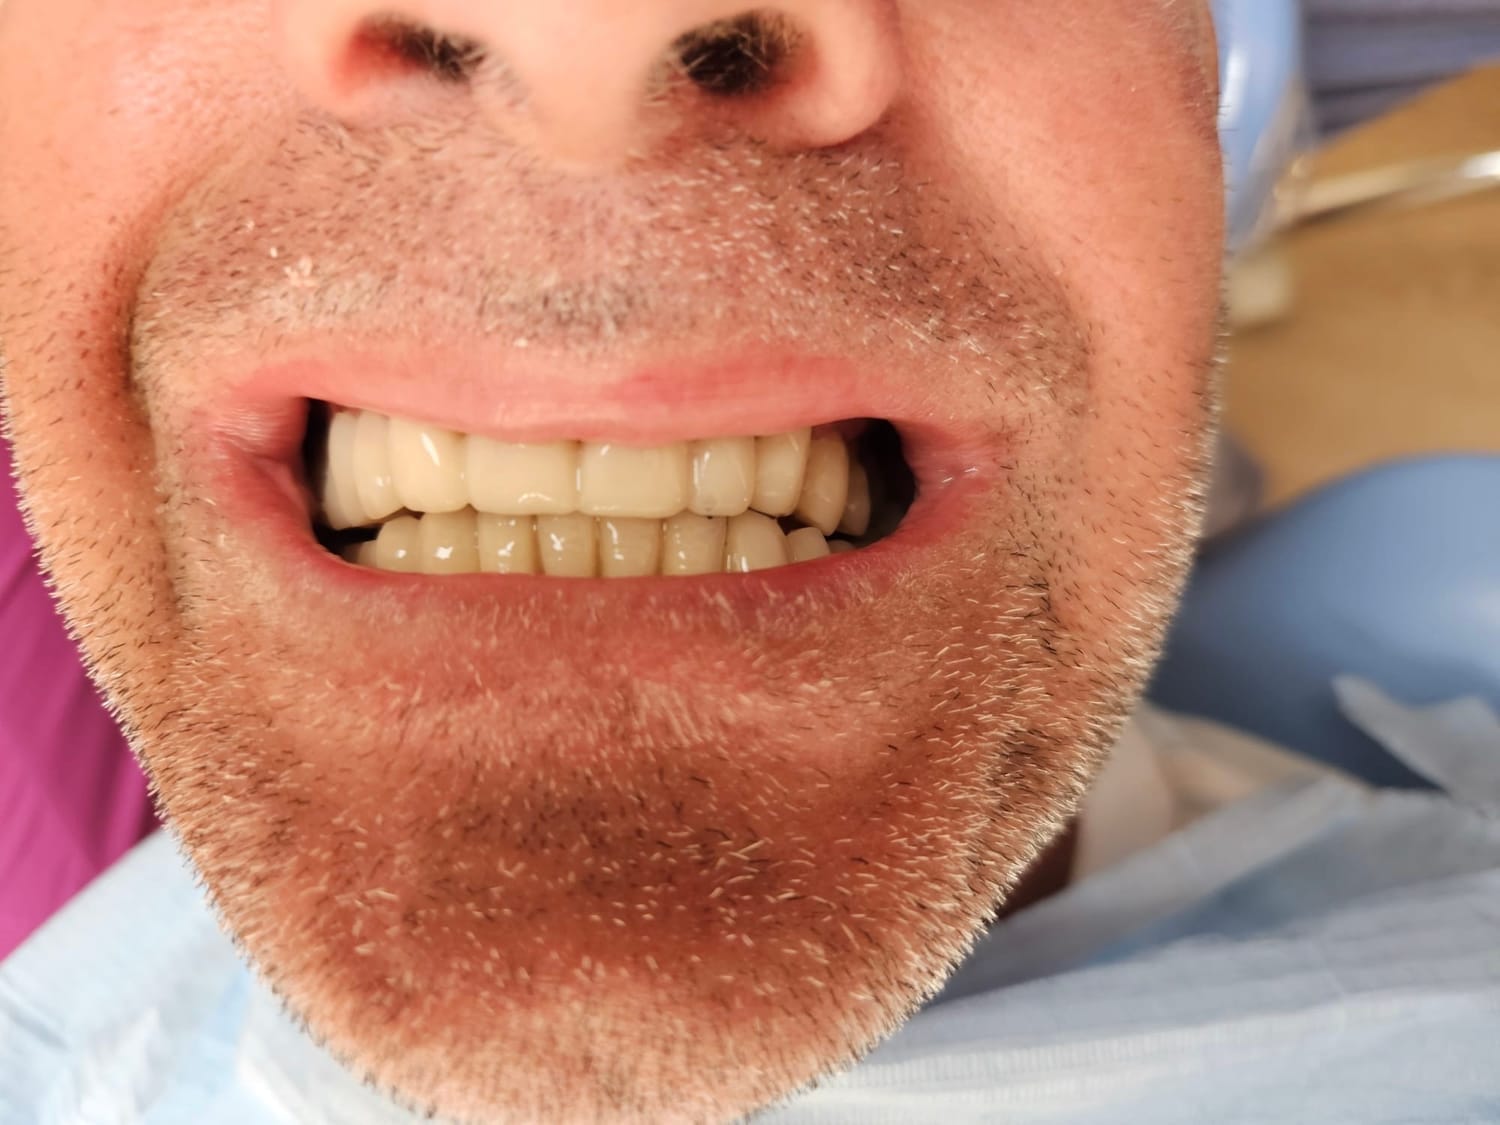

Paziente affetto da atrofia grave con parodontite acuta localizzata.

Caso progettato e realizzato attraverso la tecnica dell'implatologia computer-guidata con impianti short.

Grazie ad una progettazione fatta mediante PC su tac otteniamo preventivamente dove posizionare gli impianti la lunghezza la larghezza e la corretta angolazione di inserimento che ci consente di realizzare le protesi ancora prima di farevlintervento e di evitare tagli e scollamento gengivali che provocano dolore e bruciore riducendo notevolmente itempi di guarigione e i fastidi post intervento